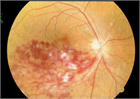

病態

1. 角膜、水晶体、中間透光体、眼底のみならず視神経から後頭葉に及ぶ視路を障害する疾患で視力低下が起こり得る。